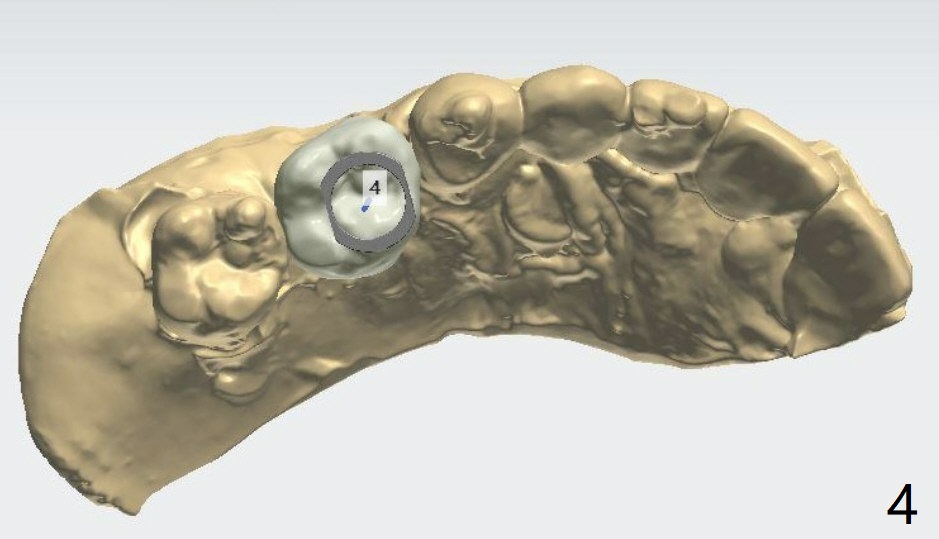

2个缺牙1个磨牙牙冠